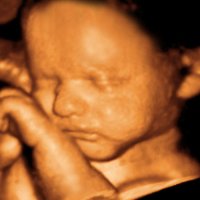

Prenatal Tanının Geleceği Maternal Kanda Fetal DNA Tayini ve Olası Tehlikeler

Bakın, medikal teknoloji günümüzde hangi boyuta ulaştı.